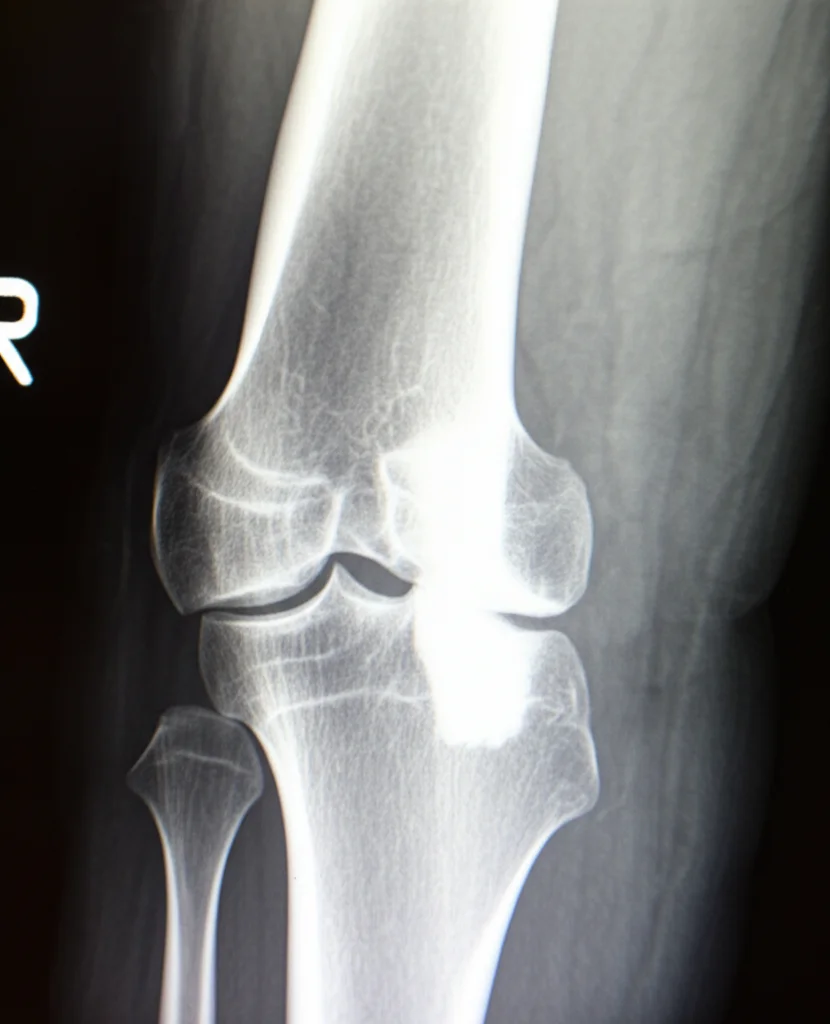

Ciao a tutti! Oggi voglio parlarvi di un osso duro, nel vero senso della parola: la displasia osteofibrosa (DOF). Si tratta di una condizione ossea benigna, un po’ un’anomalia dello sviluppo, che colpisce soprattutto i più giovani, spesso prima dei 10 anni, e tipicamente si localizza nella tibia, anche se può spuntare pure altrove (femore, radio, ulna…). È rara, rappresentando solo lo 0,2% di tutti i tumori ossei primari, ma quando c’è, pone delle sfide non indifferenti.

Immaginate una lesione fibro-ossea che cresce nell’osso, di solito nella parte corticale (quella esterna e dura) della tibia. La cosa “buona”, se così si può dire, è che tende a fermarsi quando lo scheletro matura. Il problema è che la diagnosi non è sempre immediata e bisogna distinguerla da altre condizioni come la displasia fibrosa o l’adamantinoma delle ossa lunghe.